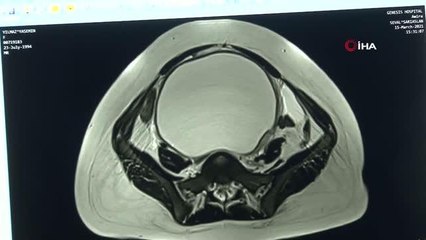

Geceleri yatarken vücudunun içerisinde hareketlilik olduğunu fark ederek doktora başvuran 27 yaşındaki Yasemin Yılmaz’ın karnından, neredeyse 9 aylık bebek boyutuna ulaşan 2 buçuk kilogramlık kist çıkarıldı.